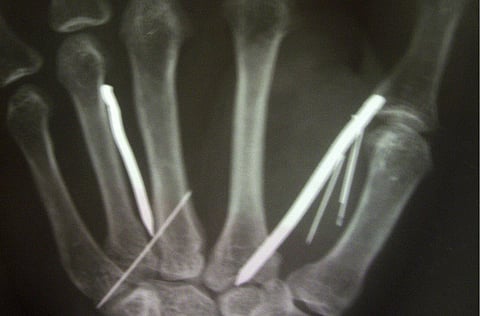

Doctors in Sri Lanka have said they removed 13 nails and five needles from L.G. Ariyawathi after she returned from Saudi Arabia last month. The items had been driven into Ariyawathi's legs and forehead.

The 49-year-old Ariyawathi has said the family she worked for in Saudi Arabia punished her by heating the nails and needles before sticking them into her. She worked in the kingdom for five months.